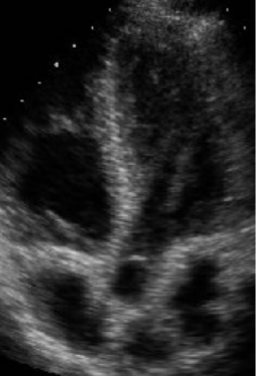

<p>What view is being shown?</p>

What view is being shown?

<p>What view is this?</p>

What view is this?

Subcostal